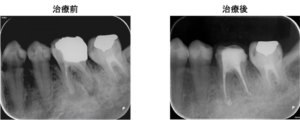

左下6番の歯の根の先に炎症があり膿が出ていたので、根の治療(根管治療)を提案し、患者様の合意を頂き治療をすすめることになりました。

左図のレントゲン写真では根の先に炎症があり骨が溶けている部分があります(矢印部) 。

根の治療9か月後のレントゲン写真です。矢印の根の先の骨の溶けている部分は無くなっています。この後、仮歯からジルコニア製のかぶせを装着されました。

奥歯は複数の根があり、根の病気になるとなかなか治癒させるのが難しいです。しかし、原因となる根の中のばい菌をしっかり除去し、抗菌性のある材料で根の中をつめるとこのように治癒に導くことができます。治療の初期に症状が全くなくなったため、患者様はとても喜ばれておられました。